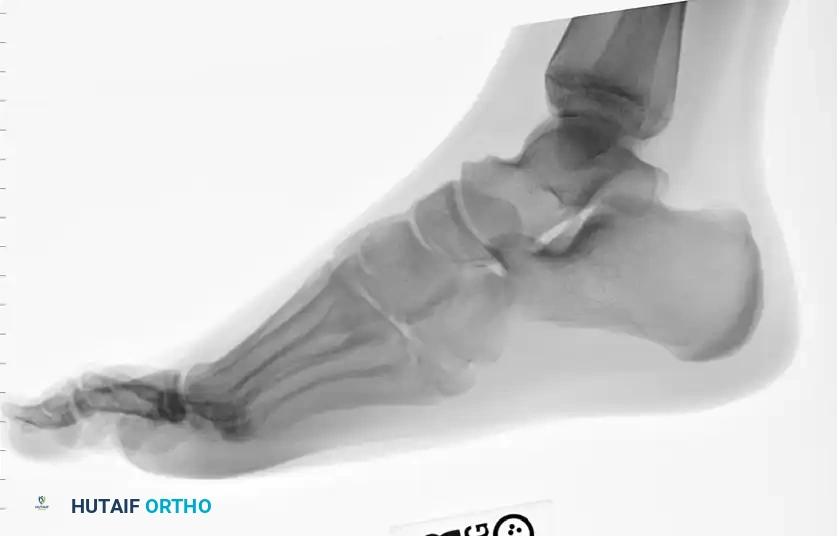

A standard three-view radiographic series of the foot is mandatory for accurate zone classification.

Lateral radiograph, essential for assessing plantar gapping and the sagittal alignment of the metatarsal shaft.